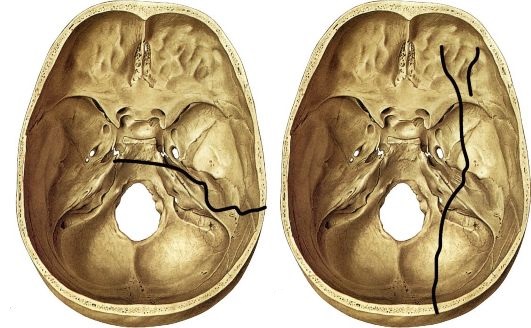

• Продольные переломы составляют более 80% всех переломов височной кости. В большинстве случаев они вызваны воздействием поперечной силы на сосцевидный отросток или чешую височной кости. Слуховая капсула в большинстве случаев не страдает, а линия перелома проходит спереди и сбоку от нее.

• Поперечные переломы составляют около 20% всех переломов височной кости. Чаще всего они вызваны ударом в область лба или темени, но причиной может стать и удар в затылок. Часто страдает слуховая капсула, что приводит к повреждению улитки и полукружных каналов.

Продольные переломы. На них приходится около 70—80 % переломов пирамиды. Возникают под действием силы со стороны черепа, которая приложена к затылочно-теменной области. Проявляются чаще трещинами, но иногда, в зависимости от силы воздействия, и большими раздроблениями кости. Типичная линия перелома проходит от чешуи височной кости вдоль переднего края пирамиды через крышу барабанной полости и заканчивается в области остистого отверстия средней черепной ямки. У большинства пострадавших повреждаются структуры среднего уха: наружный слуховой проход, барабанная перепонка, верхняя стенка слуховой трубы, сосцевидный отросток. Но лабиринтная капсула нередко остается вне перелома.

Поперечные переломы пирамиды височной кости встречаются реже продольных, но они гораздо более тяжелые и протекают с тяжелыми последствиями. Возникают они как

трещины при воздействии на череп силы в затылочно-височной, реже в височной области. Линия перелома направлена перпендикулярно к краю пирамиды через внутренний слуховой проход и лабиринт. В результате полностью выпадает функция лабиринта на стороне поражения и у половины пострадавших появляется паралич лицевого нерва. Само по себе среднее ухо редко повреждается, но барабанная полость у некоторых больных заполняется кровью (гематотимпанум) или ликвором, который через слуховую трубу вытекает в глотку, а при наклоне головы — через нос.